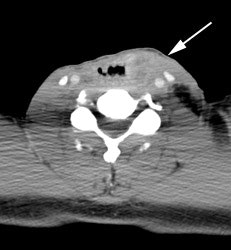

Recurrent head and neck cancer: The patient shown in the case below had a history of squamous cell carcinoma of the head and neck. The PET scan demonstrated focal tracer uptake in the left lower neck consistent with recurrent disease (black arrow on PET scan ,white arrow on CT). The PET scan also detected scattered foci of increased tracer activity within the right pleural space which corresponded to metastatic tumor implants (black arrow head on PET scan, white arrowhead on CT). |